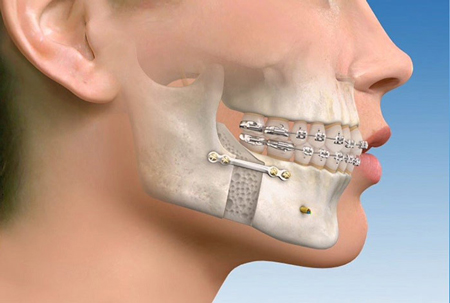

جراحی فک بالا

بیمارانی که دارای فک بالای بیرون زده هستند یا نمایش لثه های آن ها در حالت لبخند بیش از مقدار عادی است.

درصورتی که به درمانهای ارتودنسی پاسخ ندهند کاندید جراحی فک میباشند. این جراحی سبب بهبود تعادل فک و دندان ها نسبت به لب بالا و بینی و چانه خواهد شد.

پس از پایان عمل جراحی فک و صورت و پس از آن انجام ارتودنسی، دندان ها به کمک سیم و کش به هم متصل شده و ترمیم و جوش خوردن فک ها شروع می شود.